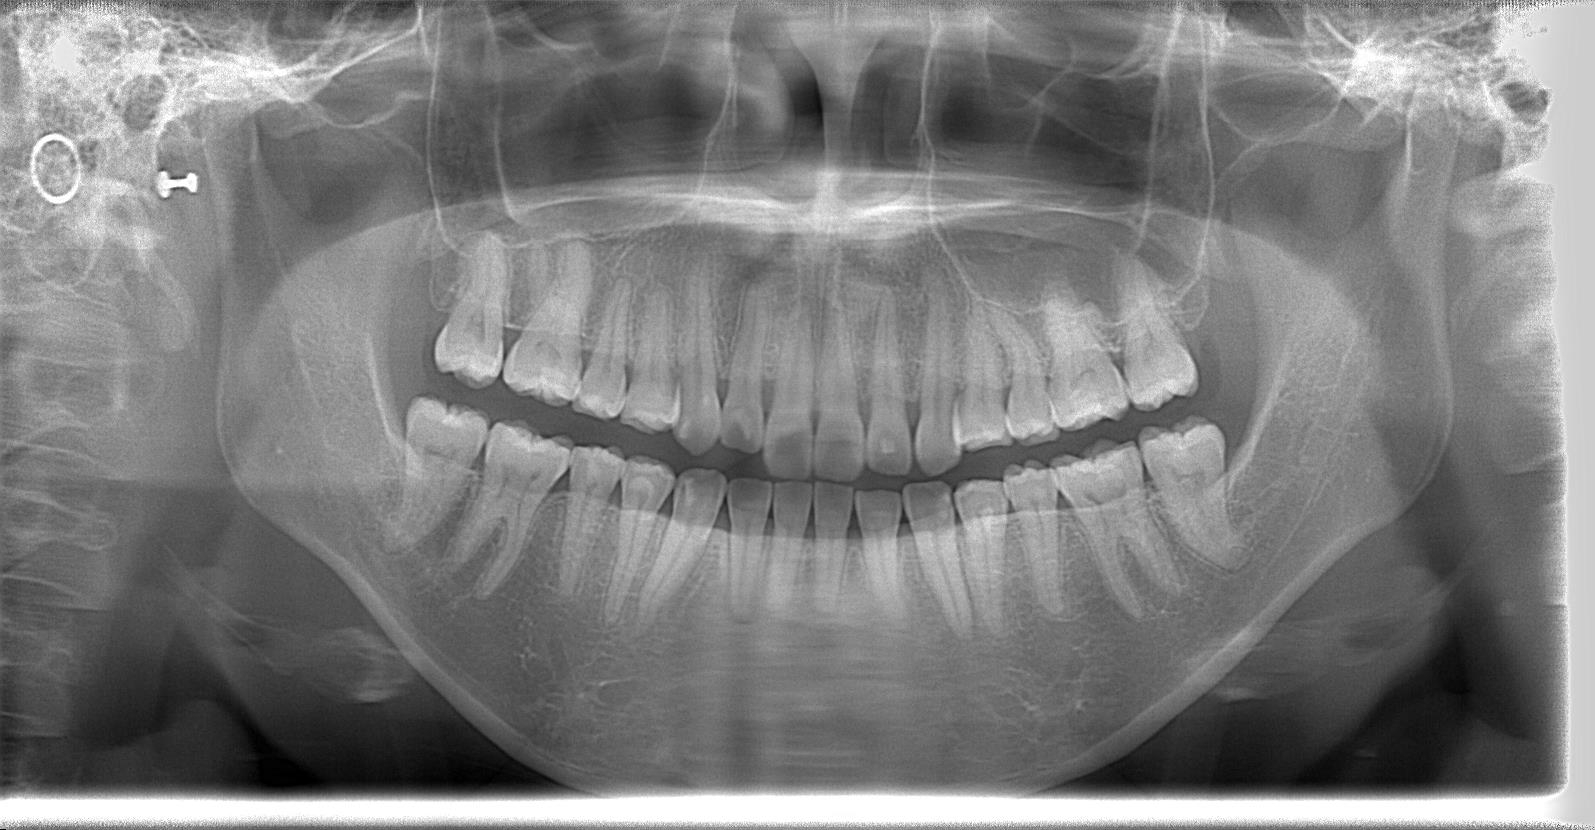

[術前パノラマレントゲン写真]

第3大臼歯を抜歯して矯正配列している症例です。